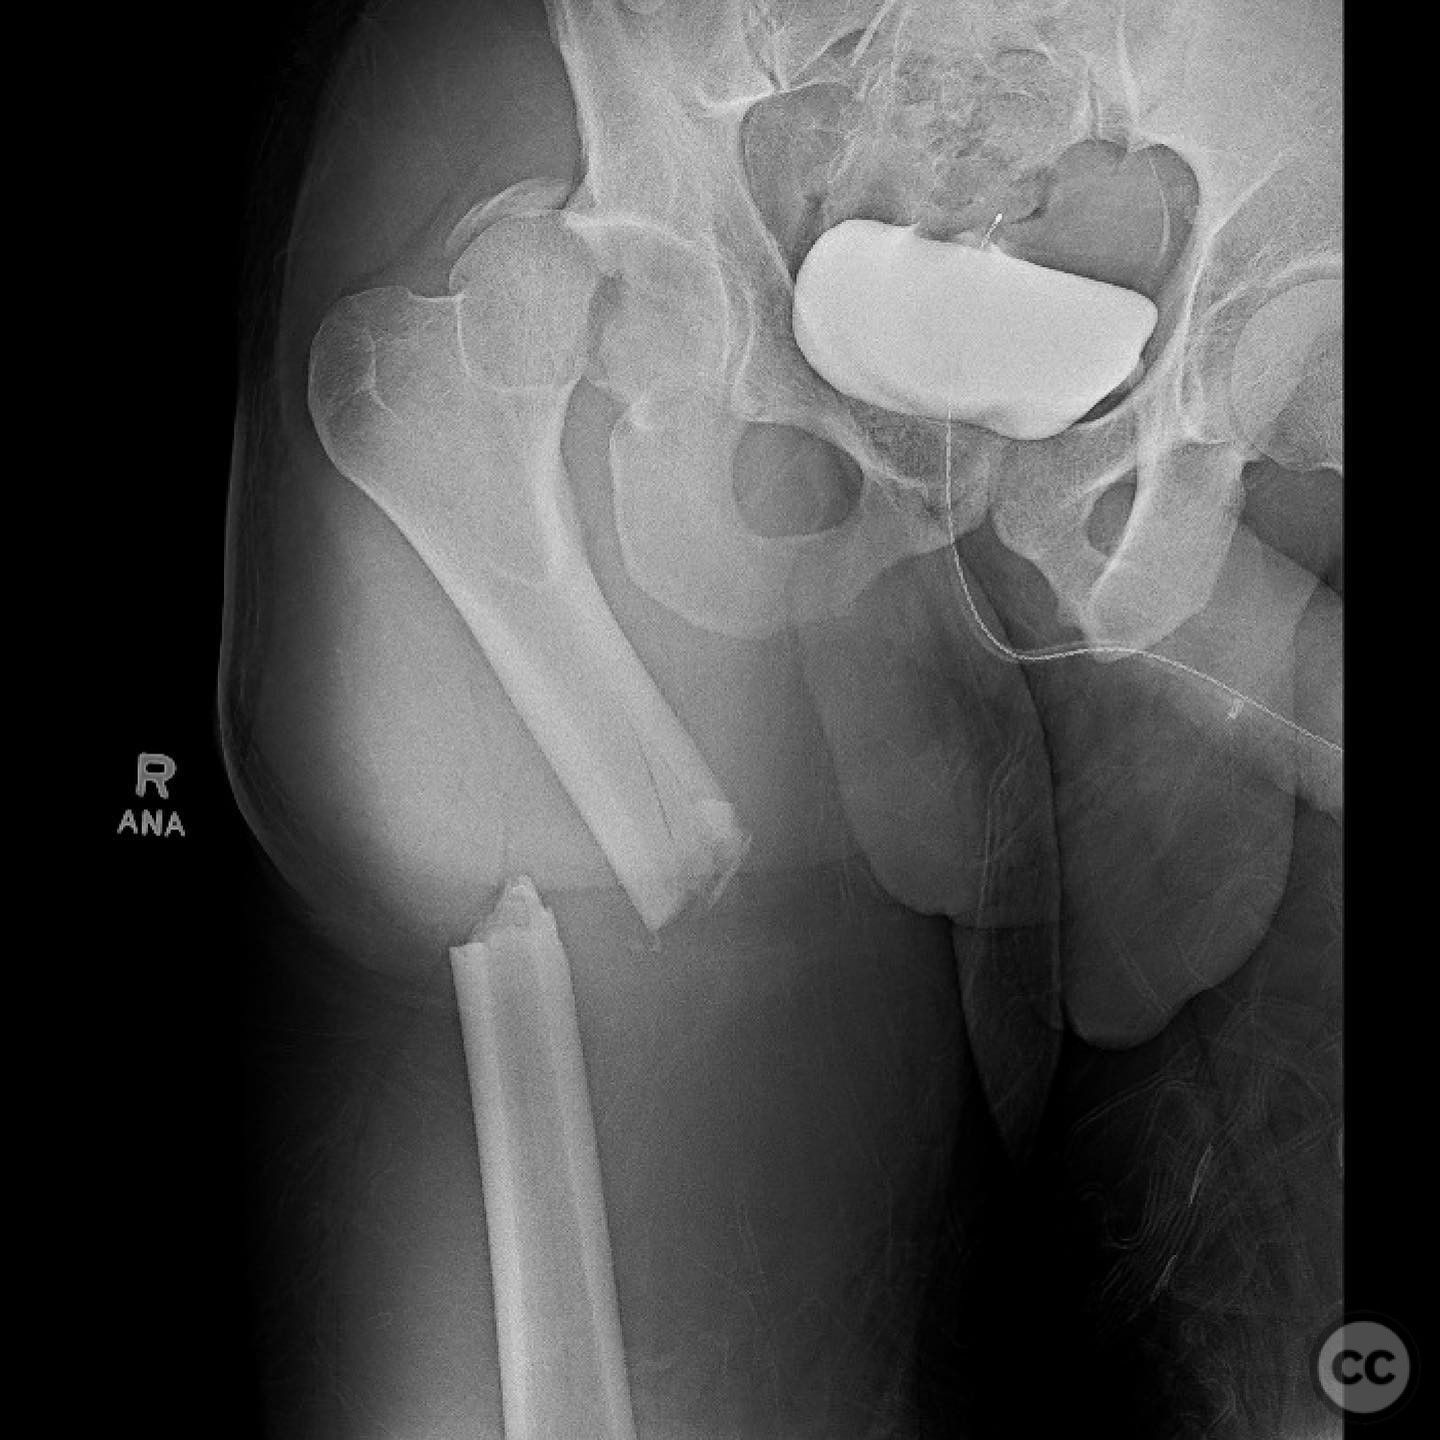

Pipkin IV Femoral Head Fracture with Ace...

Seattle, United States

Femur - AO/OTA 3x

Pipkin IV Femoral Head Fracture Dislocat...

Pipkin IV Femoral Head Fracture with Fem...

Pipkin 2 + cranial peripheral acetabular...